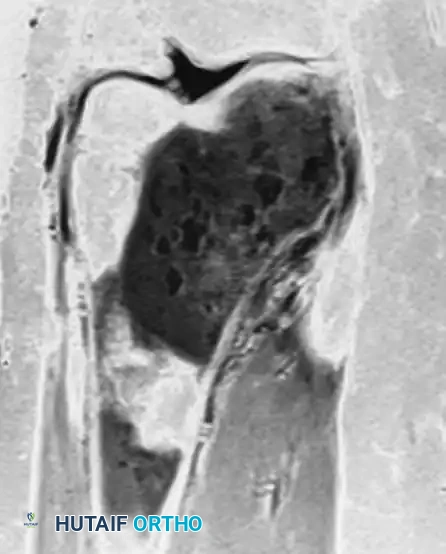

Anteroposterior and lateral radiographs of the right knee in a 51-year-old woman. The osseous structures appear relatively normal, belying the underlying pathology.

Coronal and sagittal MRI sequences of the same 51-year-old woman. The MRI reveals a massive, marrow-replacing lesion in the distal femur. Incisional biopsy confirmed a B-cell lymphoma. This highlights the critical rule: Lymphoma must be in the differential diagnosis for patients with severe bone pain and normal radiographs but abnormal MRI or bone scans.